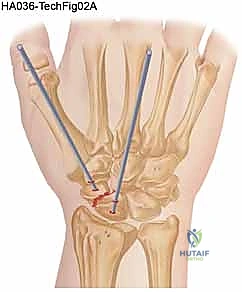

يقوم الدكتور هطيف باختيار النهج الجراحي الأنسب بناءً على موقع الكسر:

* النهج الراحي (Volar Approach): يُستخدم عادة لكسور خصر العظم الزورقي. يتم عمل شق صغير من جهة باطن اليد.

* النهج الظهري (Dorsal Approach): يُفضل لكسور القطب القريب، حيث يتيح وصولاً مباشراً للجزء العلوي من العظم، ويتم الشق من ظهر الرسغ.

هذه هي المرحلة الحاسمة. يستخدم الدكتور هطيف أحدث التقنيات العالمية، وتحديداً "براغي الضغط بدون رأس" (Headless Compression Screws) مثل برغي هيربرت (Herbert Screw). يتم تمرير سلك توجيهي (K-wire) دقيق عبر الكسر لضمان الاستقامة، ثم يتم إدخال البرغي المجوف فوق السلك.

يقوم هذا البرغي المبتكر بضغط جزئي الكسر معاً بقوة شديدة، وبما أنه "بدون رأس"، فإنه يغوص بالكامل داخل العظم ولا يبرز ليحتك بغضاريف المفصل المحيطة.